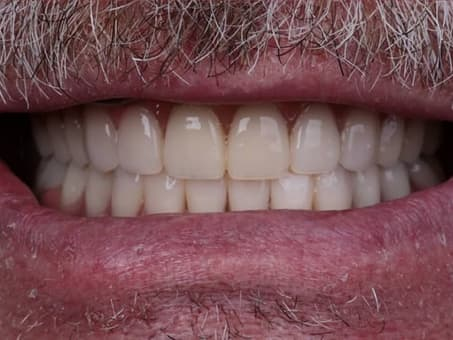

Сеть клиник «Евродент» - лучшая стоматология в Алматы, где проводится безболезненное удаление зубов как взрослым, так и детям.

Удалить зуб без боли - больше не проблема